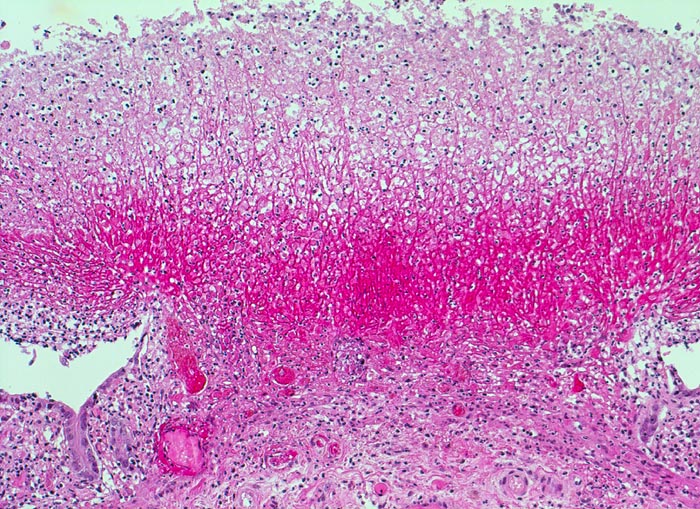

Basel 3BA HS/ Pseudomembranöse Enterokolitis

Pseudomembranöse Enterokolitis

Morphologische Merkmale:

• Herdförmige Schleimhautnekrosen.

• In den Nekrosezonen pilzförmige Pseudomembranen bestehend aus nekrotischem Detritus, Entzündungszellen und Fibrin.

• Zwischen den Pseudomembranen normale Kolonschleimhaut. Das sollte der Kliniker dem Pathologen mitteilen: